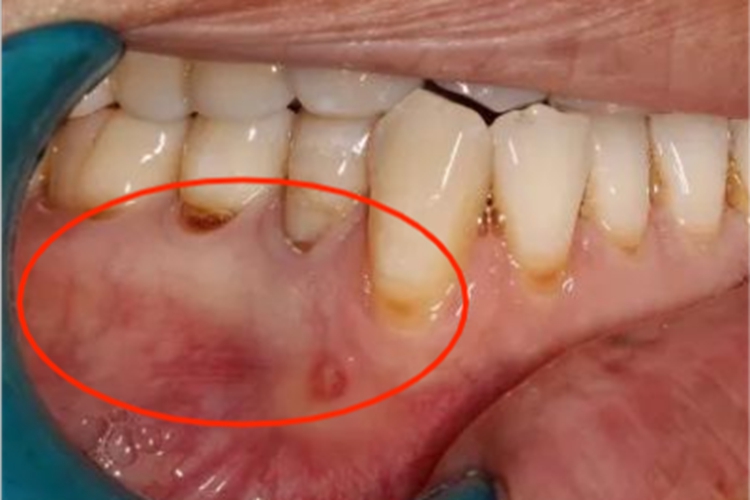

急性坏死性龈口炎多见于儿童,早期牙龈边缘及龈乳头红肿,以后迅速形成脓肿,有波动感,周围黏膜充血,患处牙龈疼痛明显,口内有特殊的坏死性口臭。

急性坏死性龈口炎是由梭杆菌和螺旋体感染引起,发生在牙龈边缘的急性坏死性口腔疾病。正常情况下,梭杆菌和螺旋体为口内共生菌,一般不感染致病,但在过度疲劳、营养不良引起菌群失调时可引发口腔黏膜病损。